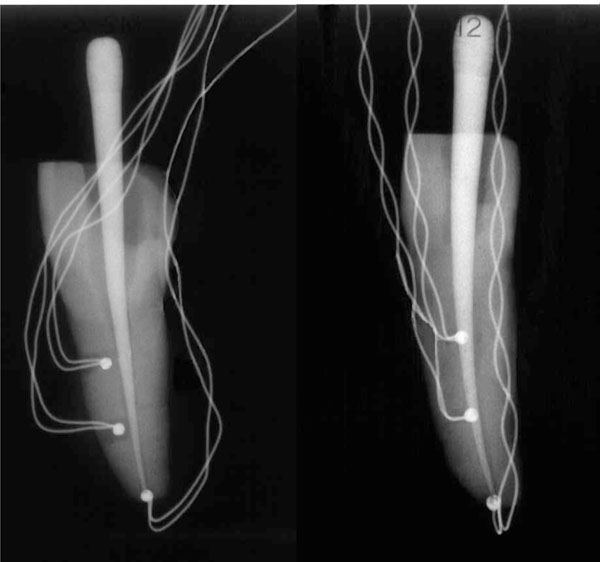

Twenty human central maxillary incisors were selected. The root portion of each tooth was scanned by a fan-beam x-ray with µCT SkyScan 1072 (Aartselaar, Belgium) at the following settings: 10 W, 100 kV, 98 µA, and 1 mm thick. 2D lateral images of the specimens were obtained through a 180° rotation around the vertical axis at a pitch rotation step of 0.90°, and the x-ray exposure time was 5.9 seconds. The set of images was then processed through a modified Feldkamp cone-beam reconstruction algorithm, and digital data were processed with reconstruction software (NRecon V1.4.0; SkyScan). Figs. (1A) and (1B) show the 3D imaging of typical roots.

3D reconstructions of selected teeth. Typical roots with an almost straight (A) or more complex (B) geometry of the root canal.

Teeth instrumented with type-K thermocouples. TA is the thermocouple positioned in the apex, while T1 and T2 are the thermocouples positioned at 5 mm and 10 mm from the apex, respectively.

A water-cooled rotating diamond ball bur (diameter, 2 mm) and a Batt bur were used to gain access to the pulp chamber and the root canal. Hence, each root canal underwent a manual sequence of K files 0.8, 0.10, 0.15, and 0.20 (Dentsply-Maillefer, Belgium). The working length was then optically measured by means of an operatory microscope [24]. Mechanical treatment through the sequence of Sx, S1, S2, F1, F2 Ni-Ti Protaper instruments (Dentsply-Maillefer) was performed following the manufacturer’s instructions. Instrumentation was performed in conjunction with irrigation by a sodium hypochlorite and ethylenediaminetetraacetic (EDTA) water solution [36]. Two holes with a diameter of about 0.6 mm were drilled along the root of each tooth. These holes were positioned at 5 mm and 10 mm from the root apex. Type-K thermocouples (RS Components, Corby, UK), namely, T1 and T2, positioned at 5 mm and 10 mm from the root apex, respectively, were inserted into these holes and cemented with Duralay resin. A third thermocouple, TA, was inserted and cemented in the root apex. X-ray radiographs were performed to verify the correct positioning of the thermocouples (Fig. 2).